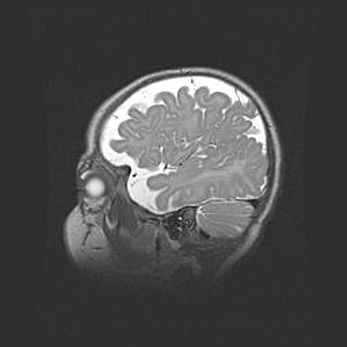

Неполная лизэнцефалия (пахигирия). Открытая гидроцефалия.

Возраст: 17 дней

Вес: 3110 г

Пол: мужской

Окружность головы: 33,5 см

Срок гестации: 35-36 недель

Лизэнцефалия—недоразвитие корковой пластинки и мозговых извилин в результате нарушения миграции нейронов коры. Поверхность мозговых полушарий гладкая. Микроскопически выявляется отсутствие нормальных слоев коры и скопление групп нейронов в подкорковом белом веществе.

Пахигирия—уменьшение числа вторичных извилин. В пораженном полушарии нервные клетки образуют толстый недифференцированный слой с неправильно расположенными нервными волокнами и группами гетеротопных клеток. Нервные клетки незрелые. Белое вещество истончено. При этом нередко аномально развит корково-спинномозговой путь.